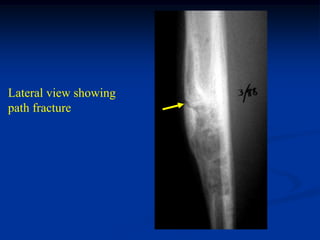

Lateral view showing

path fracture